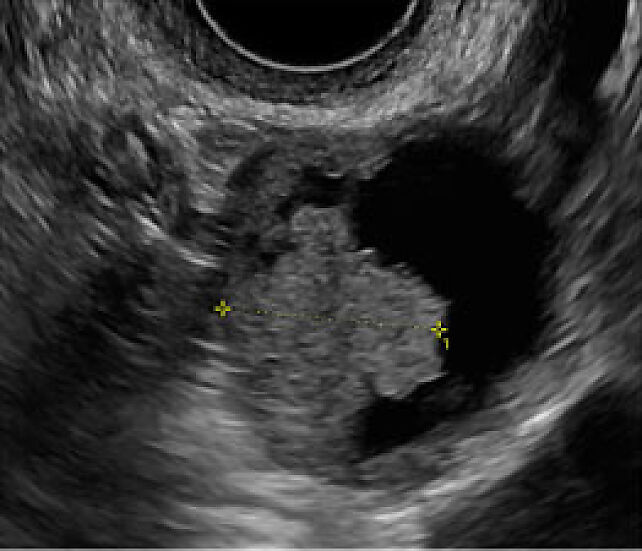

The high chemosensitivity of MGCTs contributes to their associated favorable outcomes. Most dysgerminomas are diagnosed at Stage I and, with treatment, the prognosis is excellent, with an overall survival rate of over 90% and a recurrence risk of 15–25% in stage IA. Prognostic factors for improved survival include young age, low grade and surgical intervention. Dysgerminomas are solid tumors composed of cells resembling primordial germ cells, arranged in sheets, cords and nests, with stroma containing small lymphocytes and histiocytes. A minority of cases may present scattered syncytiotrophoblastic cells, which can cause slight elevations in serum human chorionic gonadotropin (hCG). In a case series of 20 pure dysgerminomas, the most characteristic ultrasound features identified through pattern recognition included a purely solid tumor with a lobulated pattern, exhibiting heterogeneous internal echogenicity, smooth lobulated contours, well-defined borders and rich vascularization on color/power Doppler examination.21 The lobulated ultrasound appearance of dysgerminomas may be attributed to fine connective tissue containing lymphocytes that separate nodules of tumor cells, as shown in Figure 9. However, a similar ultrasound pattern may also be seen in other solid malignant ovarian tumors, such as solid metastases or lymphoma.

9

Lobulated pattern of ovarian dysgerminoma. Ultrasound examination shows a solid tumor with relatively anechoic connective tissue (yellow marks) that separates lobules. The gross specimen shows a multilobulated, fleshy, pink-tan cut surface with fibrovascular septa (yellow marks).